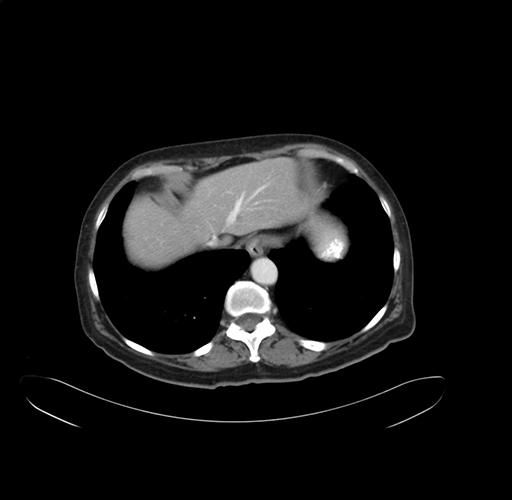

Pre-Chemo: Axial Venous

Axial Venous